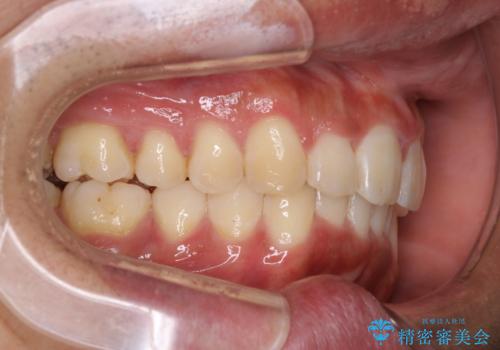

インビザラインによる出っ歯の矯正

- 出っ歯と下の歯のガタガタを主訴に来院されました。

上の奥歯を後方に移動させて、スペースを作り前歯を内側に引っ込める計画としました。

インビザラインをしっかり使用していただいたので、スムーズに治療をおえることができました。